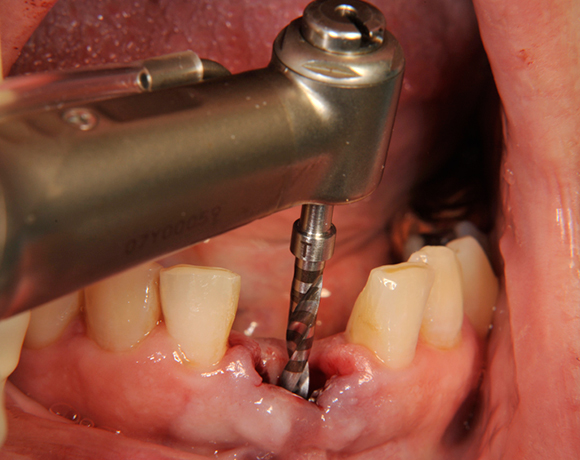

Die Keramikimplantate der Fa. Dentalpoint lassen sich auch zur Sofortimplantation verwenden. Das bedeutet, dass nach Extraktion nicht beherdeter Zähne direkt die Implantate gesetzt werden können.

Im vorliegenden Patientenfall wurden die beiden nicht erhaltungswürdigen, mittleren Unterkieferschneidezähne durch zwei Vollkeramikimlpantate ersetzt.